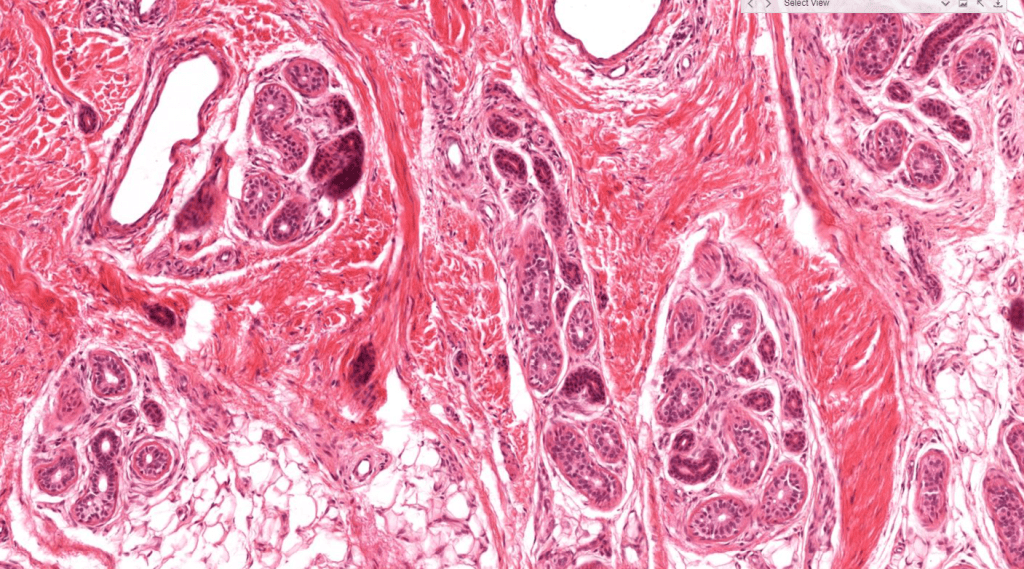

SUDORÍPARAS ECRINAS/MEROCRINAS

Ubicadas en toda la piel excepto labios y genitales.

NO asociadas a folículos pilosos.